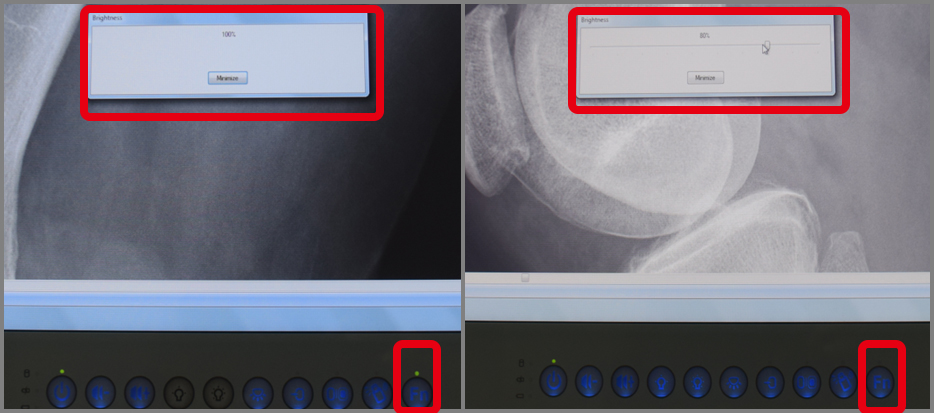

DICOM是人眼所看到的實際亮度,在電腦螢幕上用明顯的灰階呈現出來,讓X光片的顯影能夠更清晰。Wincomm提供的DICOM功能,設計概念以方便操呈現作為出發點,並提供三種色溫,符合不同地區的喜好選擇。此外特別設計亮度鎖定功能,以保證DICOM模式下,亮度的準確性。

Picture: Function Key Design, press the button to operate DICOM, brightness will be fixed

1. Compliance to DICOM Part 14 : Grayscale Standard Display Function, tolerance is less than 5%

4. Calibration interval: 6 months